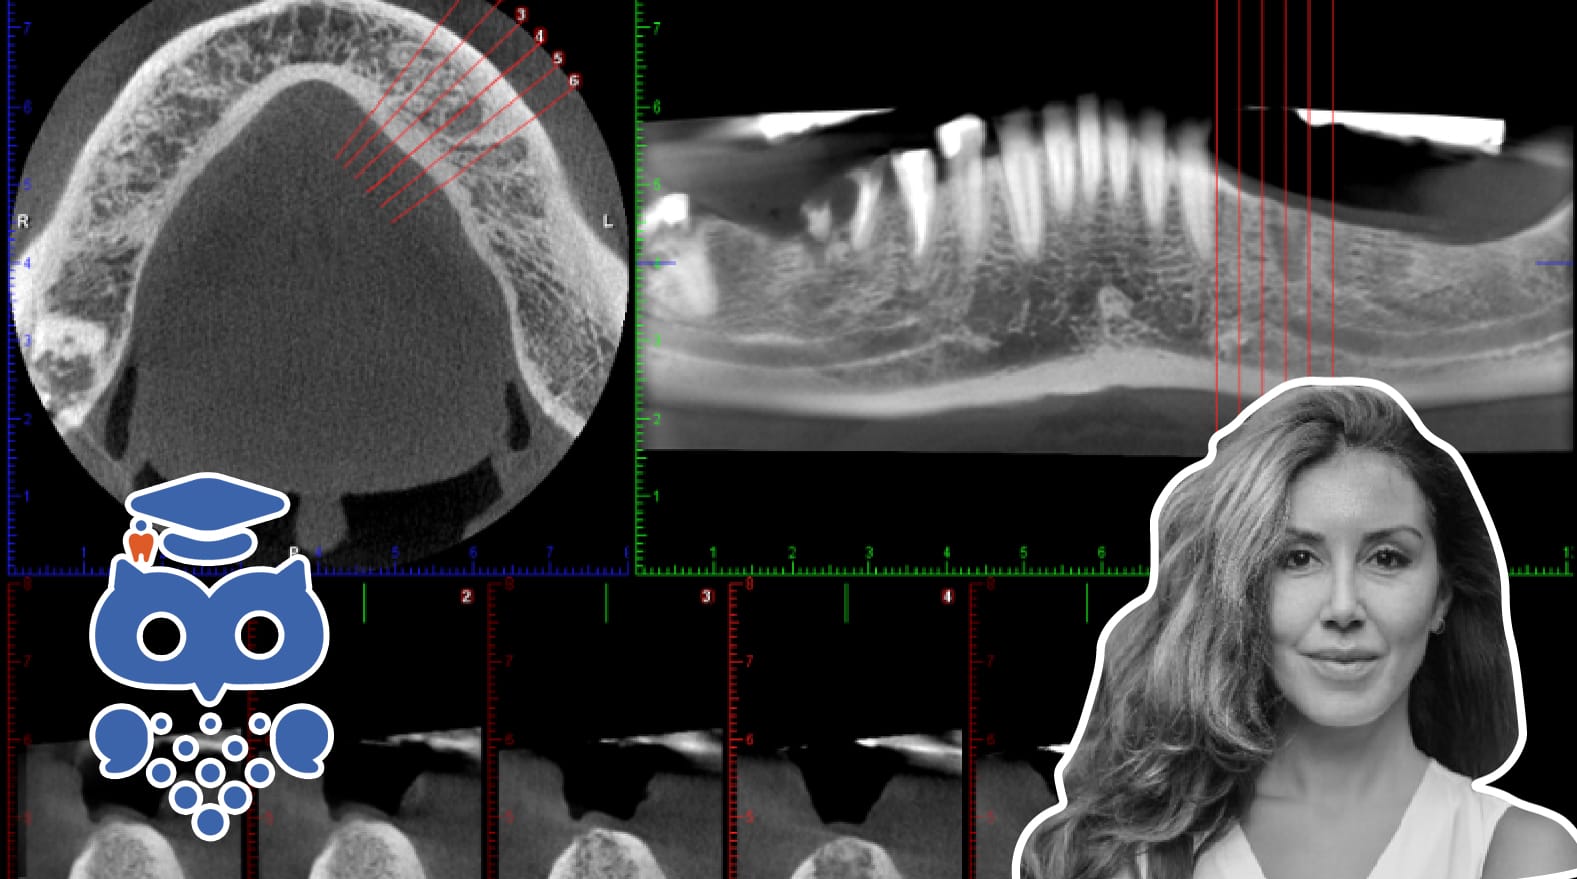

Principen för avbildning bygger på att ett kon- eller pyramidformat strålfält utgående från röntgenröret, roterar i en cirkel- eller halvcirkelformad bana runt patienten med centrum beläget antingen i medellinjen, eller inom området av diagnostiskt intresse, och en detektor på motsatta sidan av röntgenröret registrerar den röntgenstrålning som passerat patienten (Figur 1).

I samband med rotationen skapas ett stort antal projektioner och ur dessa framställs en digital volym från vilken bilder rekonstrueras i tre mot varandra vinkelräta plan; axiala, coronala (frontala) och sagittala (Figur 2).